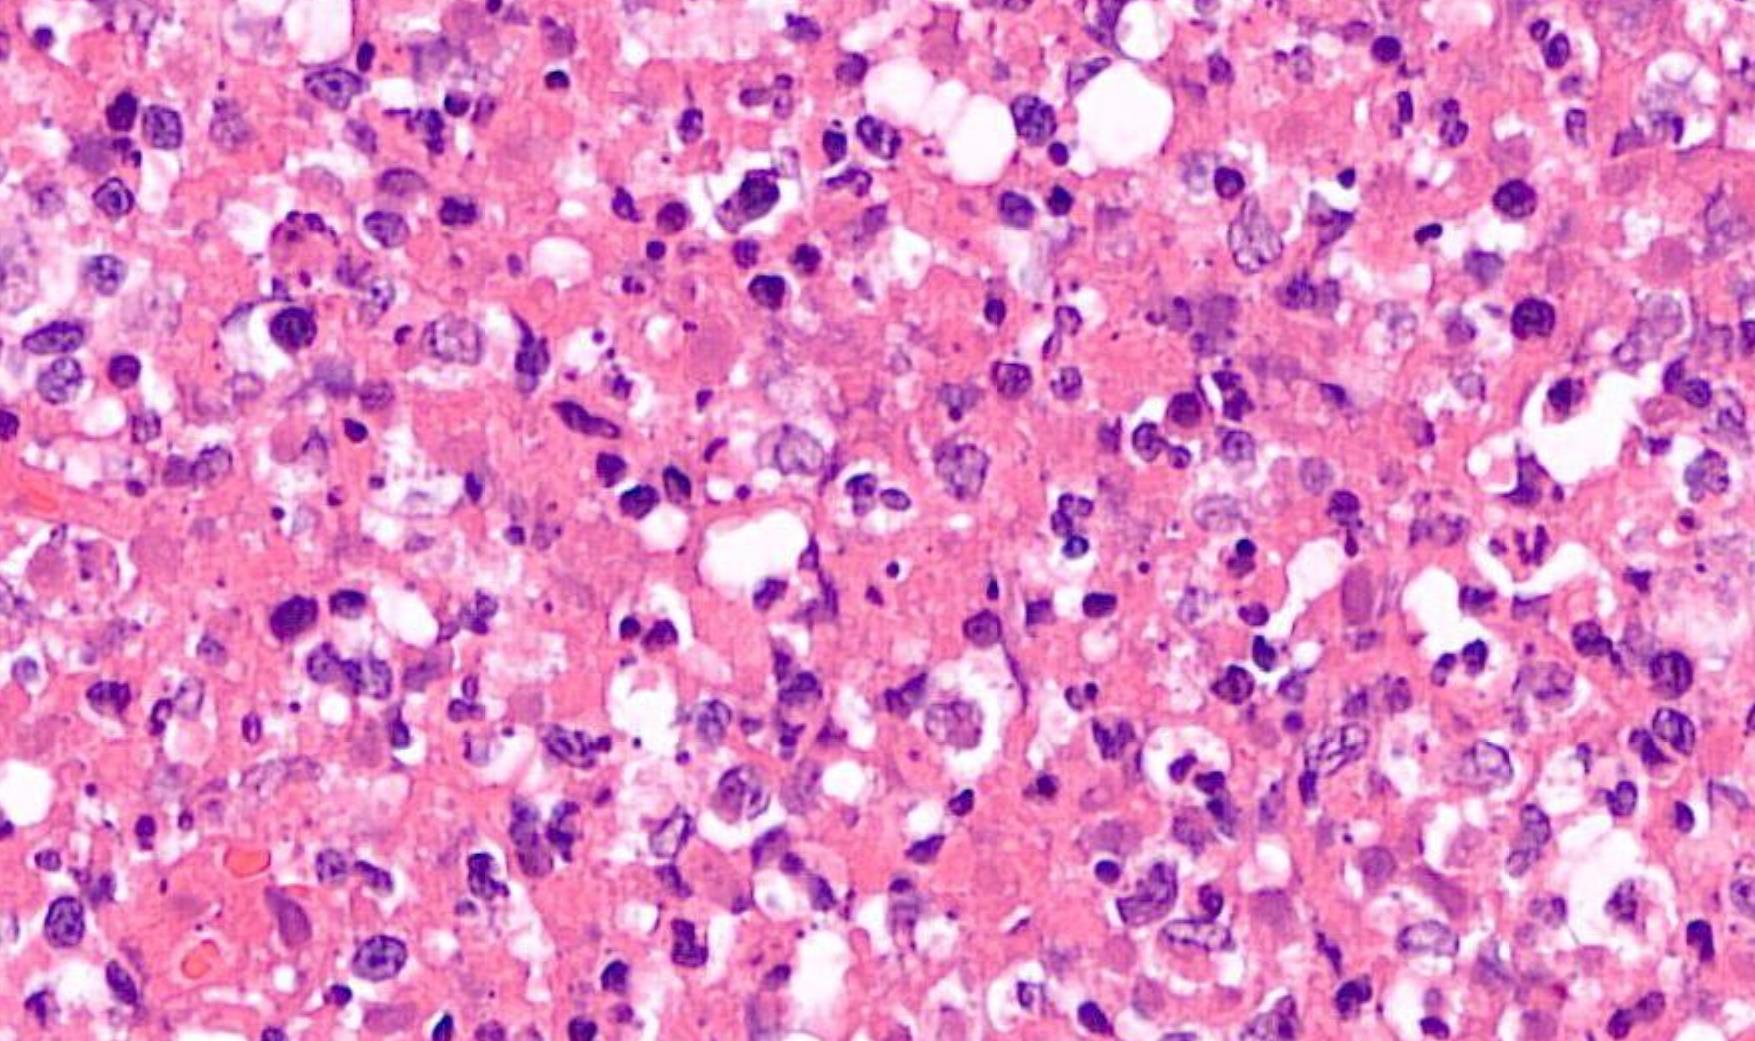

Mucosal melanoma

• 80% of head and neck MM- nasal cavity, septum, maxillary sinus • In the oral cavity-maxillary gingiva and palate • Flat pigmented lesions • Tumour cells are polymorphic • Lentiginous/pagetoid growth pattern • All head and neck mucosal MM are T3–4 and stage III-IV • T3 Tumour limited to the epithelium and/or submucosa (mucosal disease) • T4a Tumour invades deep soft tissue, cartilage, bone, or overlying skin • Oral pigmented patches DD • Melanotic macule • Smokers melanosis • Amalgam tattoo • Naevi